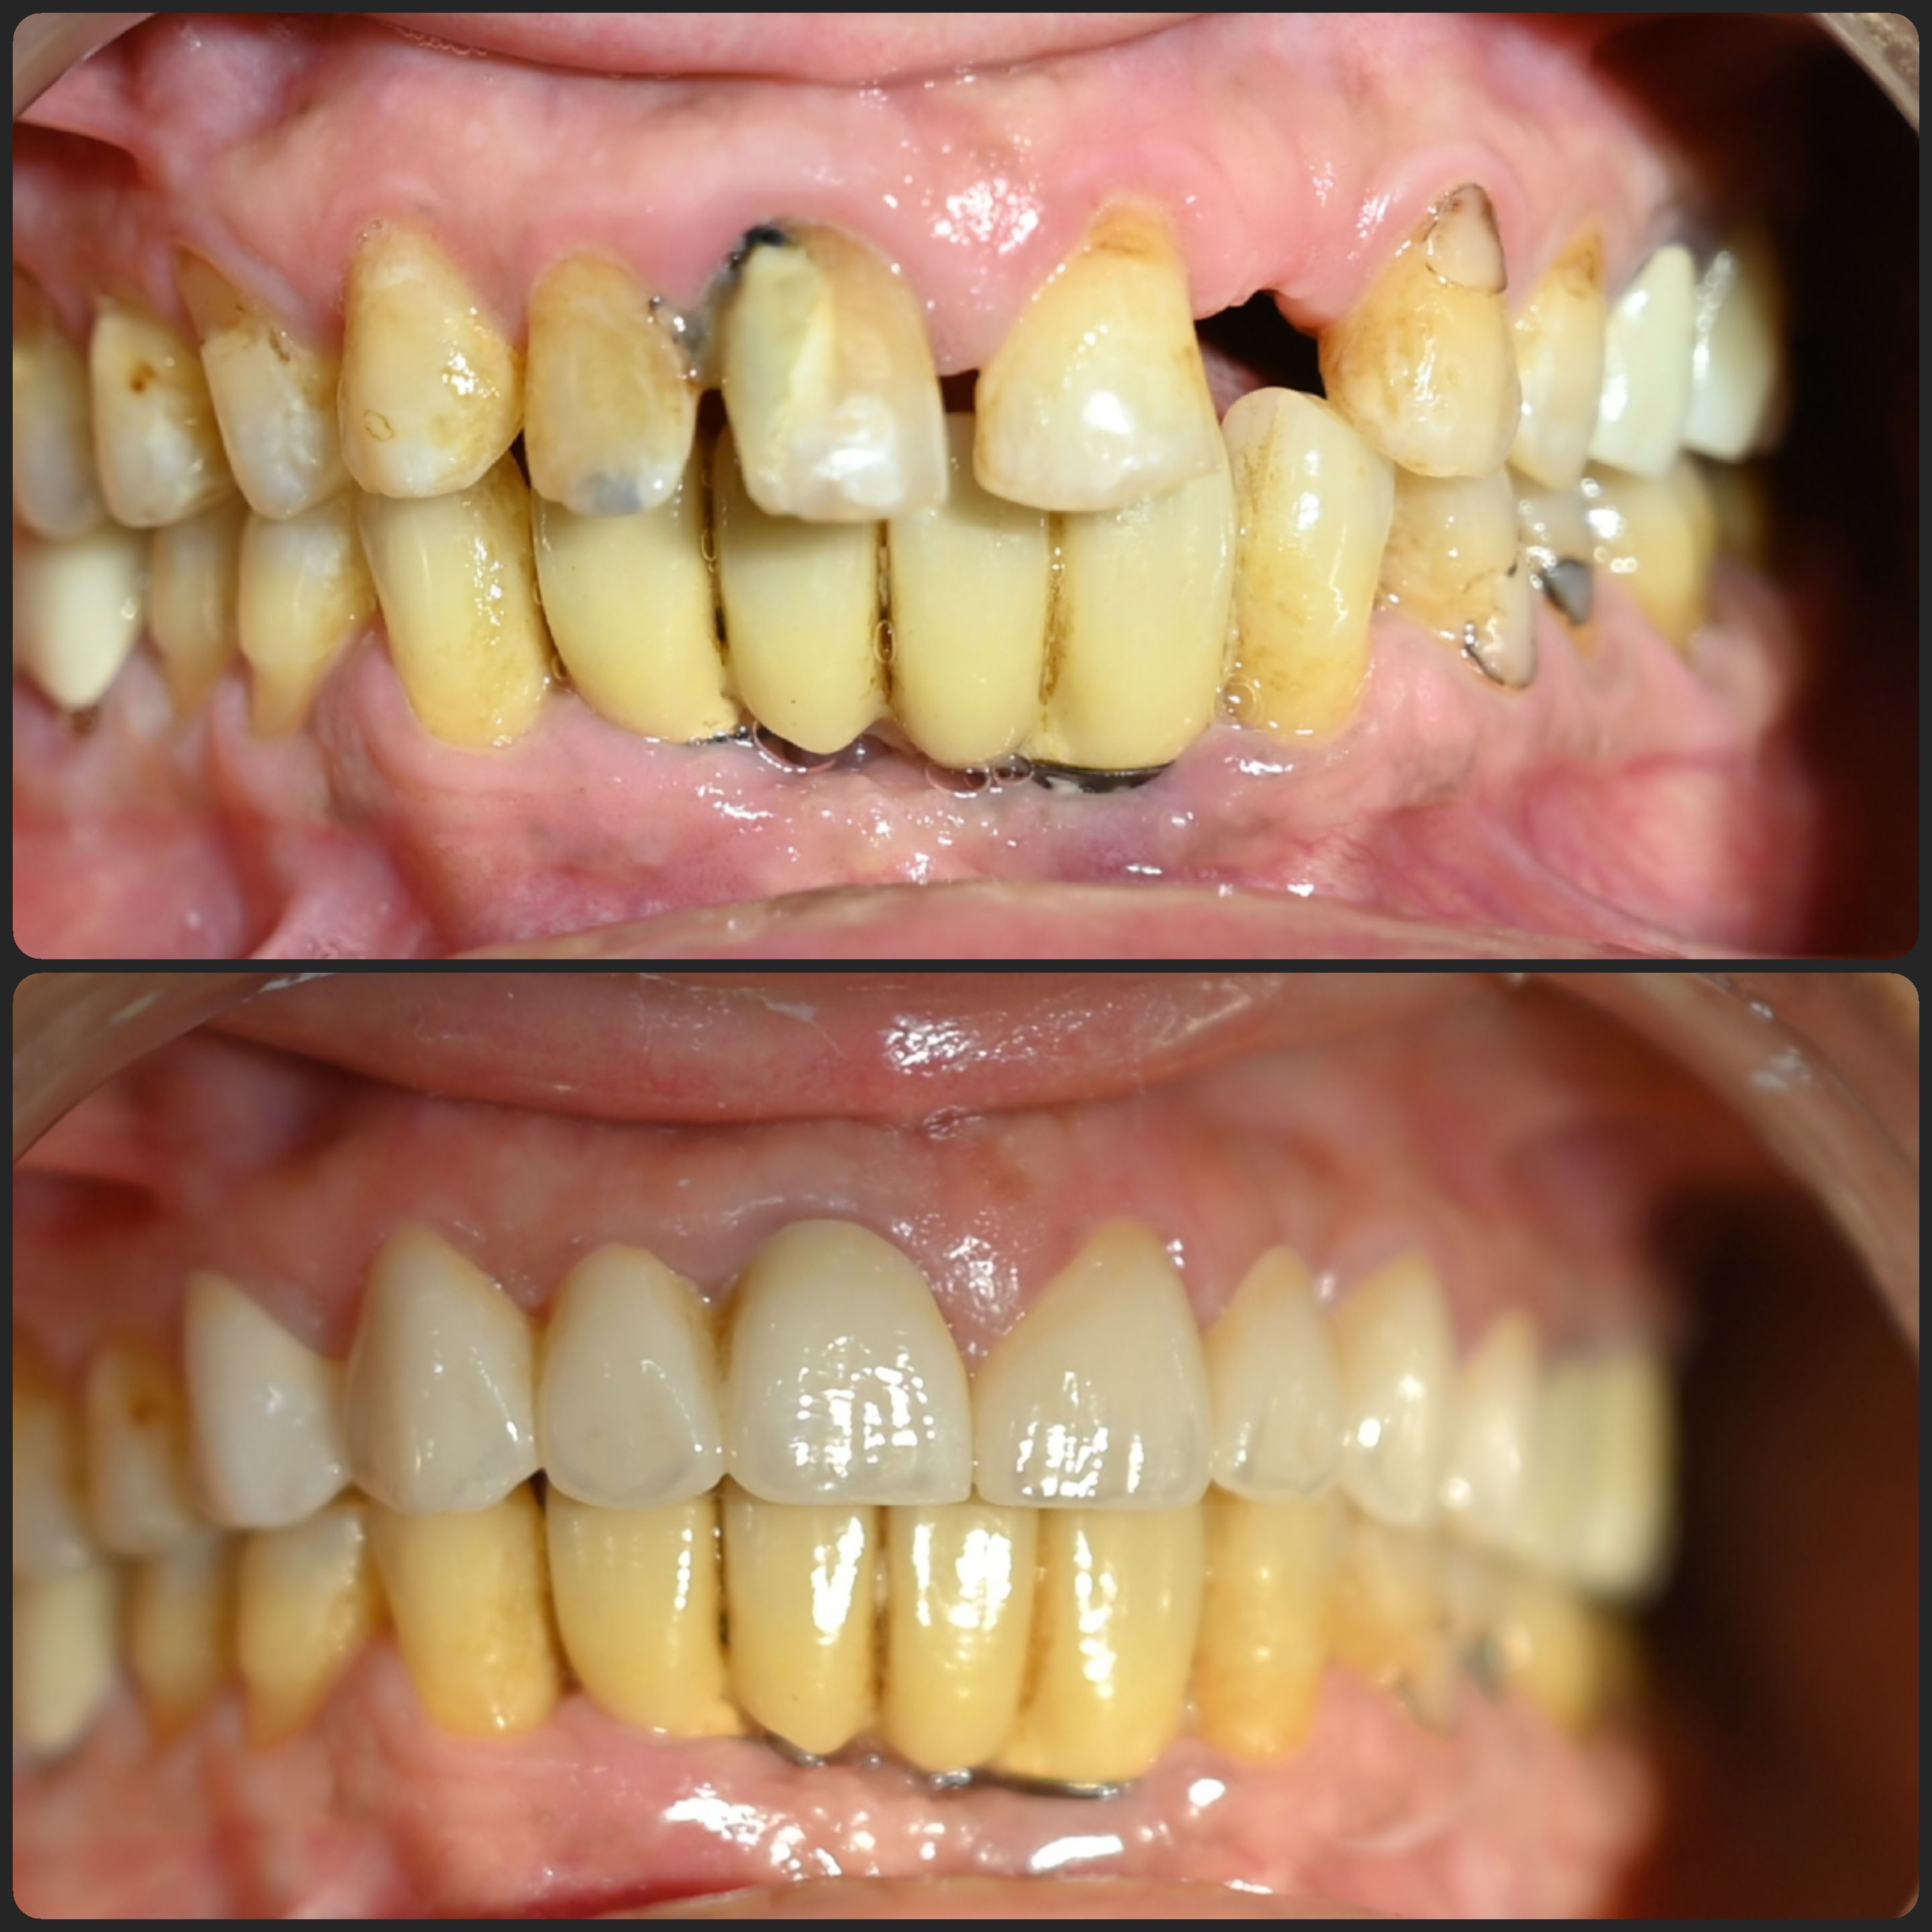

Cases